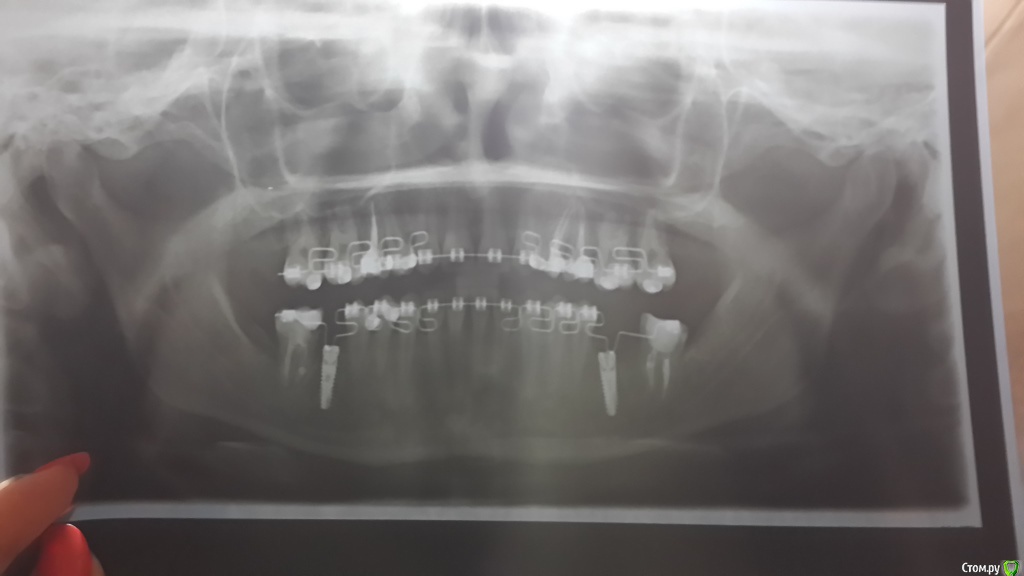

Добрый день. У меня возникло пару вопросов:

1) можно ли на имлантант Xive установить абатмент Alpha Bio

2) У меня очень далеко сместили правую семерку внизу (лечение на брекетах), можно ли до протезирования нарастить на нее пломбу(сбоку) чтобы на ней коронка была больше, а на рядом стоящий имплантант             ( вместо шестерки) установить относительно небольшую коронку?

3) Нужно ли мне перелечивать каналы нижних семерок

4) Вместо нижней правой шестерки имплантант установлен криво. Решит ли эту проблему угловой абатмент

Ортопантомограмму прилагаю. Спасибо.

По вашему снимку ответить на этот вопрос однозначно нельзя

по панорамному снимку оценивать как стоит имплант нельзя, если угол выраженный, поможет угловой или индивидуальный абатмент

Почему?? по ортопантомограмме нельзя определить? там ведь корни видны. В принципе меня интересует второй корень левой семерки. Я не вижу на ней пломбы в канале.

Потому что маникюр к Вас хороший, а снимок нет.